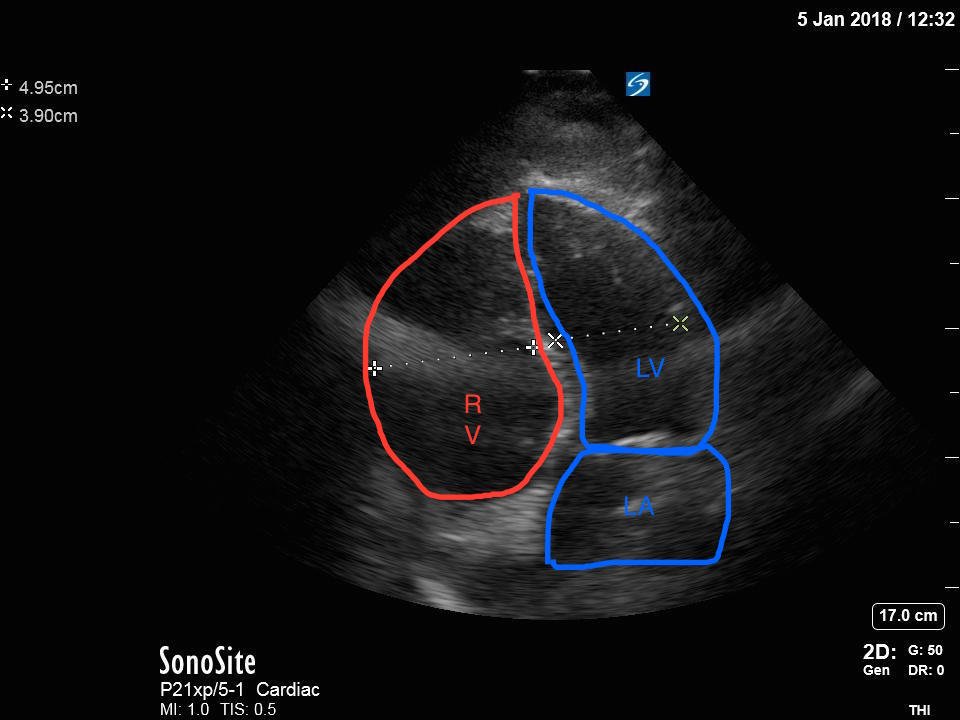

Bedside echocardiography four chamber view revealed enlarged right ventricular (RV) to left ventricular (LV) ratio (greater than 1) on apical four-chamber view (see red and blue outlines respectively). The right atrium is not clearly delineated in this image and therefore is not outlined. One can also rule out a large pericardial effusion as the cause of her dyspnea, since there is no large hypoechoic collection surrounding the heart on either four- chamber view or parasternal long view.

Point of care ultrasound is a powerful tool that can aid in the diagnosis of undifferentiated dyspnea. Right ventricular size is one parameter that can signify right heart strain possibly due to an increase in resistance in the pulmonary vasculature. The normal RV should be approximately two-thirds the size of the left ventricle. Any RV between two-thirds and equal to the size of the LV is considered moderately dilated, and any RV greater in size than the LV is considered severely dilated.1,2 The RV to LV size ratio is best measured from the apical four-chamber view. Right ventricular shape will also change as afterload increases in the pulmonary circuit. As pulmonary vascular resistance increases, the RV (which has significantly less myocardium and thus greater compliance as compared to the LV) begins to lose its typical triangular shape and takes on a more rounded appearance.3 Likewise, the intraventricular septum becomes flattened during early diastole due to higher RV:LV pressures causing the LV to take on a “D” shaped appearance. These findings, collectively referred to as signs of “right heart strain,” typically improve with resolution of the clot burden.4